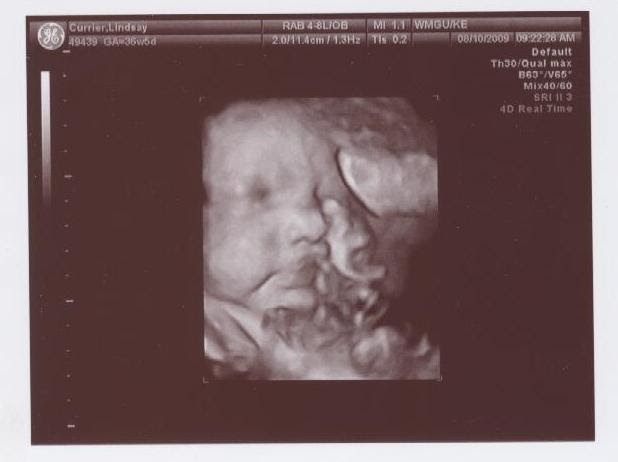

3d ultrasound 37 weeks. I have a doctors appt on the 7th ill be 37 weeks and 1 day pregnant. The purpose is just to make sure my son is head down. While it was amazing to see my son the tech was very inexpirenced and nobody told me at 35 weeks the baby is too big to get a great picture. At this stage the baby has put on some weight and filled out to make features more visible yet still enough fluid in front of babys face to obtain great images.

Has anyone had an ultrasound around 37 weeks and the babys pic looked deformed. 3d ultra sound 37 weeks severelawless. Is that common for ultrasound pics. What it would look like now that youre 37 weeks pregnant your baby is full term.

Vaginal discharge or spotting. So i had my 3d ultrasound done around at 28 weeks and didnt get one good picture. However we do recommend a gestational age of 26 34 weeks for the best facial detail. 3d 5d ultrasound images and 4d ultrasound video can be obtained at any stage.

February 2011 in 3rd trimester. You might notice an increase in vaginal dischargeif you see some bloody show mucus tinged with a tiny amount of blood in the toilet or in your undies labor is probably a few days away. Medical pregnancy scans ivf fertility scans 7834 views. It says 4d real time on the pic but was done at the local hospital just to be checked for fetal growth not a 4d ultrasound i paid for.

Pregnancy symptoms during week 37. 3d ultrasound at 37 weeks. But now im really regretting that i didnt go backdo you think its too late now. A 37 week ultrasound might be performed as part of a biophysical profile.

Learn whats going on with your little one at this part of your journey together. I made the mistake of spending 200 on a 3d 4d ultrasound. Will i still be able to get a good look at him or will he look like the.